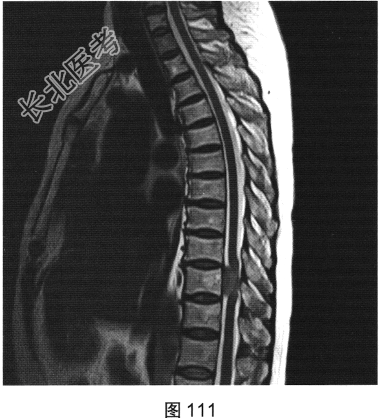

- [材料题] 患者女性,59岁,无明显诱因出现腰背部疼痛伴双下肢麻木1年,久行、久坐、久站或咳嗽、排便时疼痛加重,休息后症状缓解,1个月前腰背部麻木疼痛突发加重,行走100米既感疼痛难忍,伴双下肢无力疼痛。查体:脊柱无明显侧弯,相当于T₁₀平面以下感觉减退,腰椎活动度受限,无紧张,棘突旁压痛、叩痛,向双下肢放射。挺腹试验阳性,跟臀试验(+),双侧直腿抬高试验(一),双下肢小腿外侧、足背感觉稍差,双侧

背伸肌肌力4级;肌张力正常,双侧巴宾斯基征可疑阳性。实验室检查:人类白细胞抗原B27阴性(一),RF<10U/ml(正常值0~15U/ml)。

- 简答题2、患者行MRI检查,如图111~图114所示。根据患者病史及影像学检查,请问其最可能的诊断是什么?